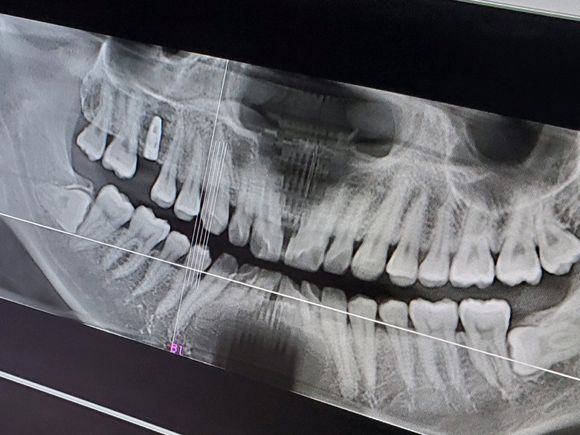

在进行种植牙手术之前,患者需要先进行一个简单的检查。有的医生会说你牙槽骨不行,骨量不够,那么牙槽骨骨量不够是什么意思?很多人认为“老掉牙”是人老了以后的自然现象,即便是缺牙后也并未引起足够重视,没有及时进行治疗,导致牙齿长期缺失,出现牙槽骨吸收严重、牙龈萎缩等现象。这种情况还能做种植牙手术吗?

牙槽骨骨量不够是什么意思?骨量不够,指的就是各种原因导致的牙槽骨收缩和骨量的一个流失。其中,牙周病是牙槽骨收缩的主因,骨量少的首要原因是牙周病。牙周病导致牙周软组织抵抗力下降,使寄生于口腔的细菌大量繁殖,牙周组织形成牙菌斑和炎症感染发生,并逐渐蔓延到牙根、牙槽骨,产生牙齿松动乃至脱落,持续降低成骨细胞活性,最终导致牙槽骨萎缩、骨质流失。所以,牙周病患者在种植牙前,需要对牙周病进行治疗,使牙周组织能够长期形式良好的功能,营造一个良好的口腔环境。

相信到这里患者就知道医生说的牙槽骨骨量不够是什么意思了。总之对于牙槽骨量不足的情况,医生会在检查后给出判断,能否做种植,之后再制定专属种植方案。而植骨的方法也是多种多样的,最终由医生专业的骨质评估后进行选择的。